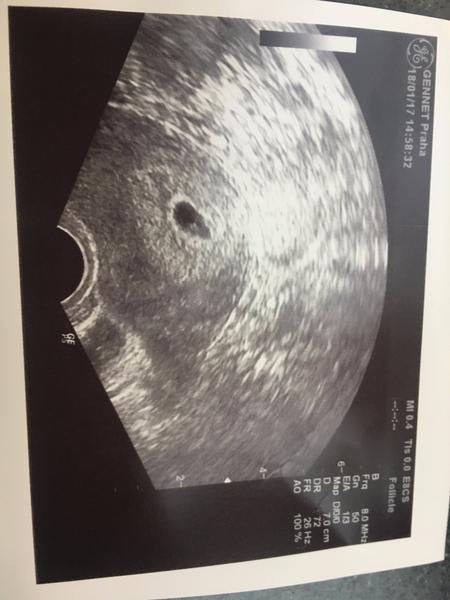

dnes jsem dle menstruace 7+0, poslední ms 28.12. , ovulace 11.1. Dnes jsem byla poprvé na utz, dělohu mám hodně vzadu, jakoby vpáčenou a stočenou do zad + mám nadváhu, dr mi dělal vaginální utz, v jeden okamžik jsme viděli plodový váček, ale pak zase vůbec nic, jsem z toho hodně špatná, miminko je vymodlené, dle dr prý přirozeně není možné v mém případě otěhotnět...sám dr tohle nazval jako neuvěřitený zázrak, vzhledem k velmi rozsáhlé endometrioze.

Holky je možné, že za týden když půjdu na utz, že už něco bude vidět? To budu 8+0 dle ms. Já dnes čekala i srdíčko, ae prostě nic, jen mi řekl, že nic nevidí, pak mi mačkal hodně břicho a na vteřinku se tam objevil ten plodový váček, ale že by viděl něco uvnitř to neříkal :(

Holky díky, já mám opravdu velkou nadváhu, takže je to u mě opravdu těžké, brala jsem první měsíc clostík tak jsem měla dělat testy abych věděla zda ovulace vychází a vyšlo to právě na toho 11.1. Na utz jsme viděli fakt jen sekundu tu bublinku jako máš ty, ale nic víc, hend se to ztratio a bylo to hodně v mlze... to bdue týden nervů :( děkuji holky